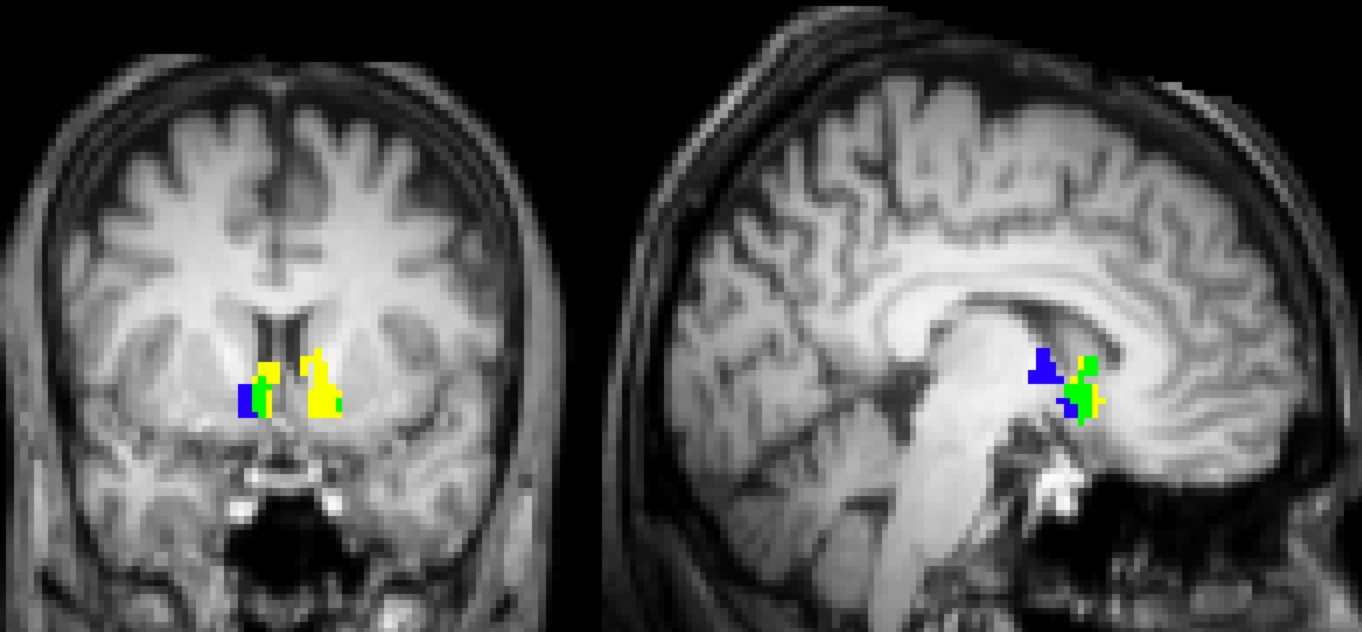

• Yellow: activates with $ to subject

• Blue : activates with $ to charity

• Green: overlap, activates with both

"Neural Responses to Taxation and Voluntary Giving Reveal Motives for Charitable Donations."

William Harbaugh, Ulrich Mayr, Dan Burghart. Science, June 15, 2007. Full text here.

The image shows that getting money for yourself and seeing a charity get money activate very similar reward related areas of the brain. Individual differences in the magnitude of these activations help predict who will give voluntarily. Brain activation is higher when people give voluntarily than when they are taxed - but funding for the public good is lower.